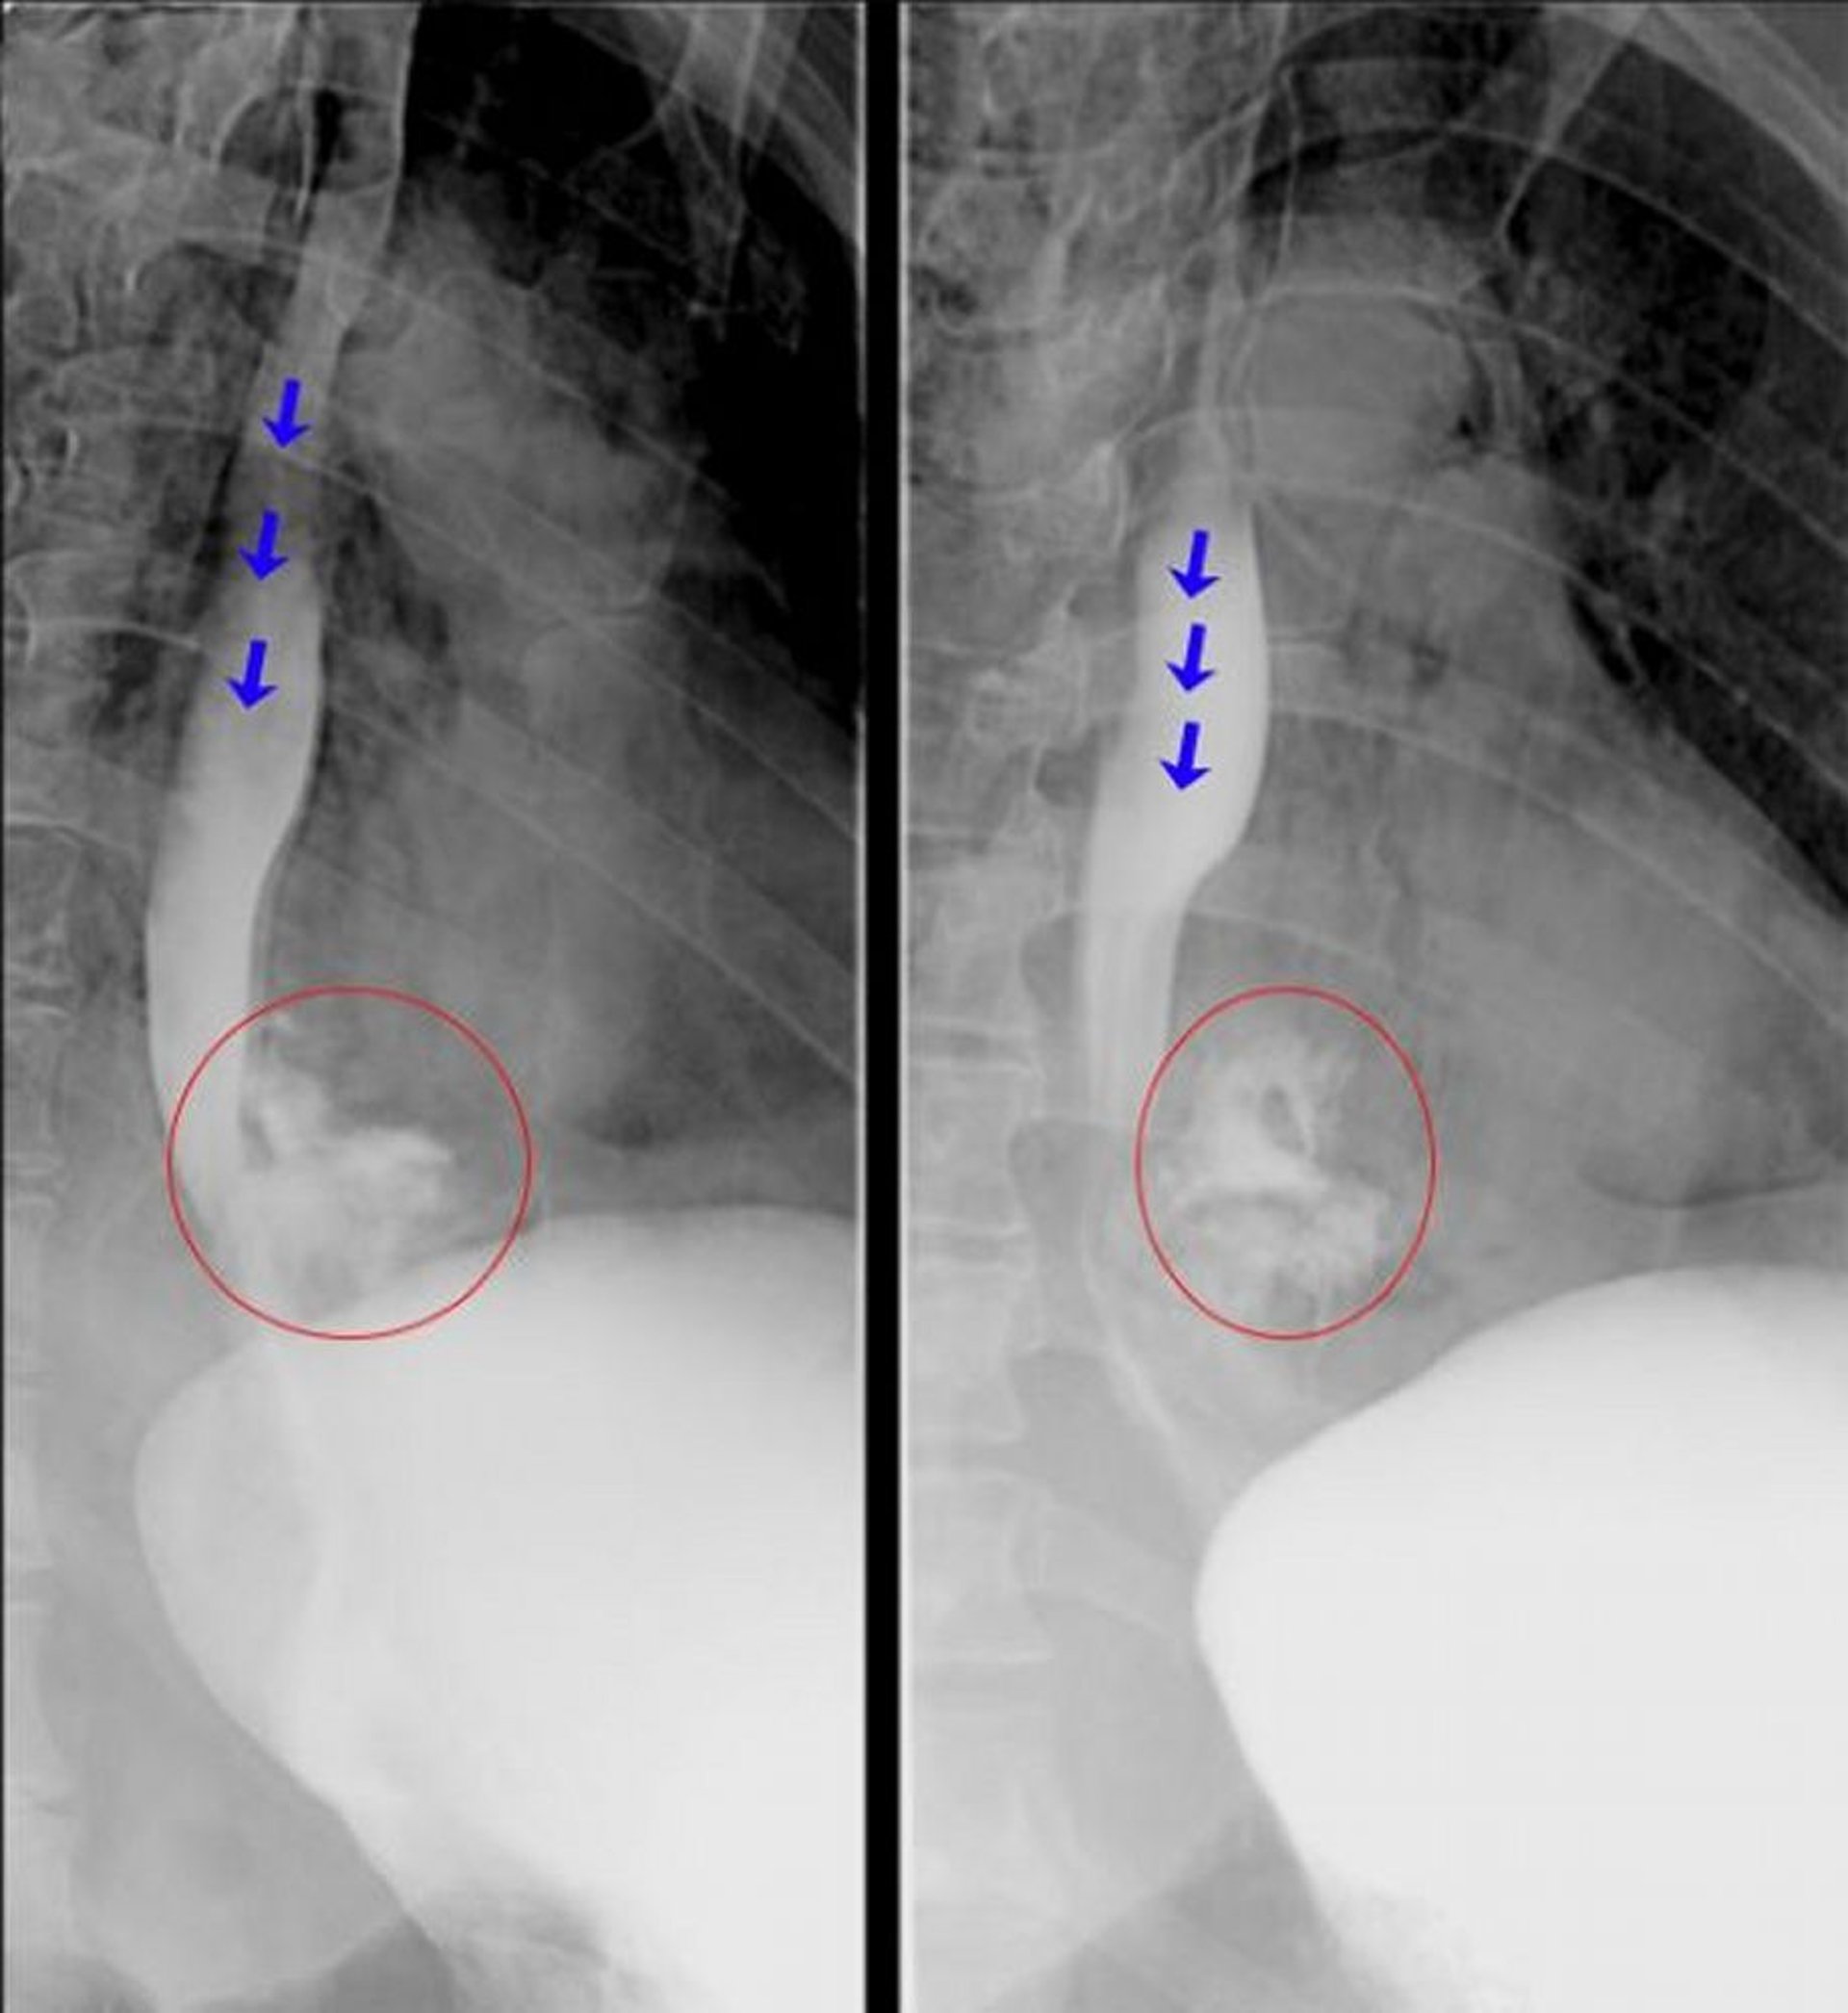

Esofagografía con medio de contraste hidrosoluble del diagnóstico

Estos esofagogramas fluoroscópicos muestran una extravasación franca de material de contraste del esófago distal compatible con una perforación esofágica. Las flechas azules destacan el material de contraste dentro de la luz del esófago. Los círculos rojos destacan el material de contraste extravasado del esófago.